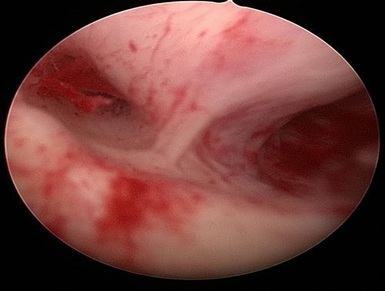

Hysteroscopy showing Polyp in Uterine Cavity.

Hysteroscopy showing Multiple Endometrial Polyps inside Uterine Cavity.

Three-Dimensional Ultrasonography (3D USG) in comparison to hysteroscopy is less invasive, cheaper, easily accepted by most patients and does not require much training. In most cases an endometrial polyp can be differentiated from the submucous fibroid based on the imaging characteristics. The polyps are typically round in shape, smooth in outline, and are generally echogenic, compared to the endometrium or are isoechoic to it. The underlying endometrial-myometrial interface is preserved (Figure 5). Moreover the presence of a vascular pedicle has a positive predictive value of up to 81.3%. Fibroids are more inhomogeneous, hypoechoic, and there is a loss of endometrial-myometrial interface. The percentage of the intra cavitary portions of the submucous fibroids i.e., grade of submucous myoma can be assessed on 3D USG by the degree of distortion caused by it (Picture 6).